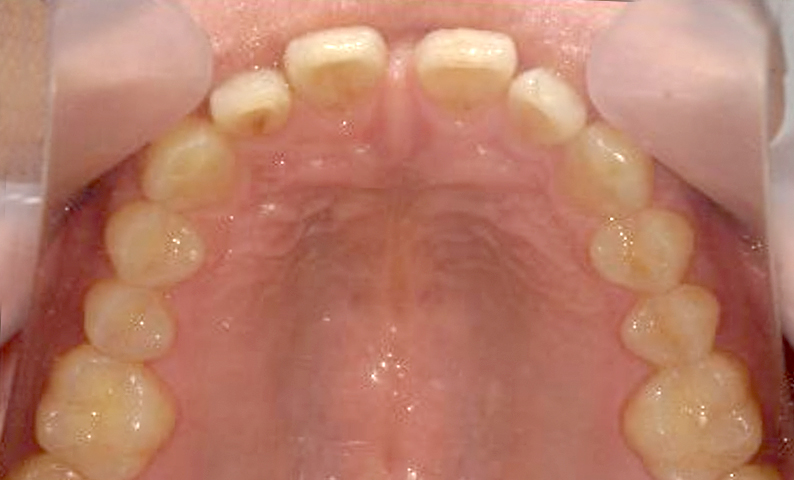

| 治療前 | 治療後 |

|---|---|

|